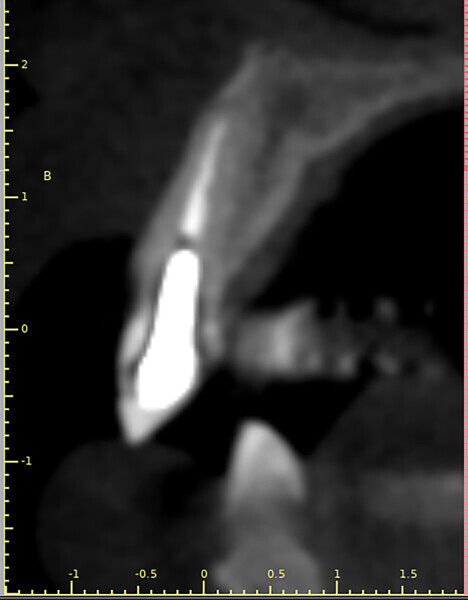

Fig. 2: The trajectory of the root

in relation to the alveolus can be visualised with a cross-sectional image.